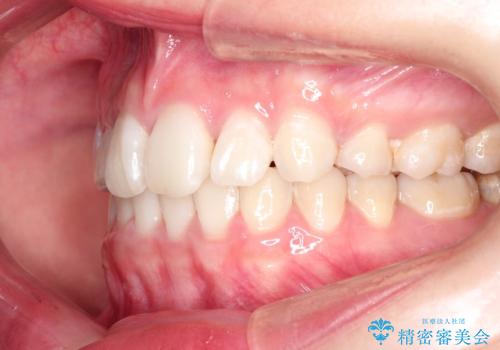

ハーフリンガル矯正 抜歯をして前歯を下げる

- 上顎の両側第1小臼歯抜歯による抜歯矯正を計画した。

上顎の抜歯により上の前歯の位置を大幅に後ろに下げることができます。

奥歯の位置関係など、様々な要素を加味し、適応を判断する必要があります。